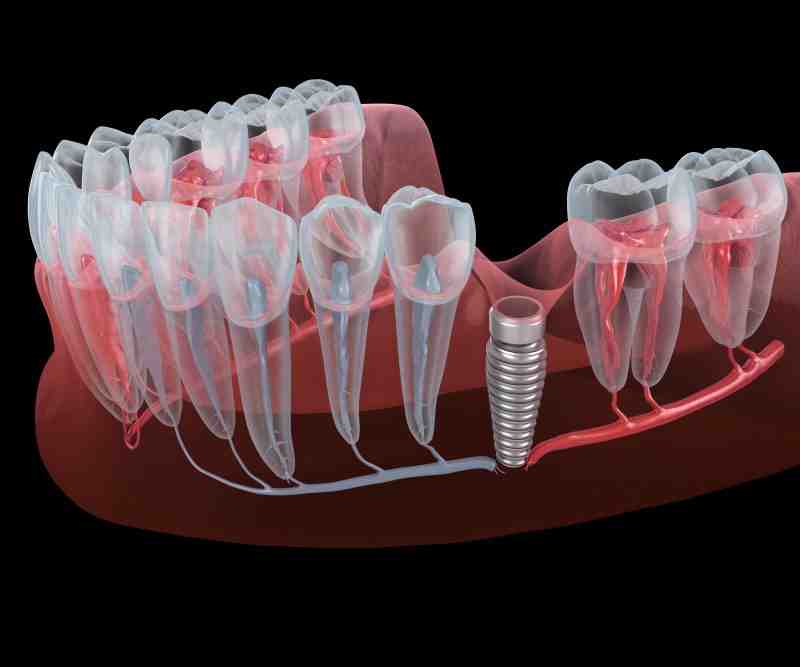

How do they remove dental implants?

Removal process The dentist first uses local anesthesia to put the patient’s jaw and gums to sleep. Next, the dentist removes the crowns, followed by abutment. Using dental instruments, the dentist then removes the screw and then removes the gums.